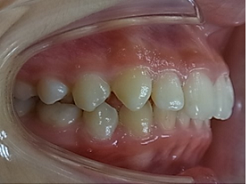

当矯正歯科医院では非抜歯で治療をしています。

治療後の後戻りが矯正では問題となりますが歯を抜かないで治療しているため、後戻りも最小限で済みます。

初診時

終了時

術後3年後

術後4年後